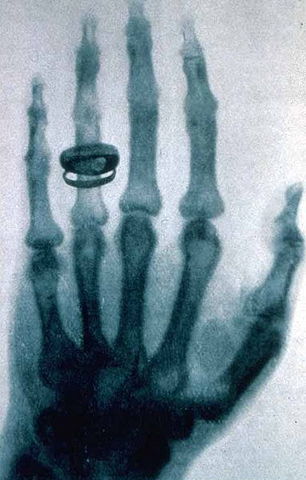

• Raig X

Raig X

Roentgen va ser el investigador i dexcobridor dels raigs X. Els raigs X son radiacions electromacnetiques invisibles que travessen capes. El 22 de desembre Roetngen va fer la primera radiografia del mon a la seva dona, on apareix la fotografia amb el anell posat.